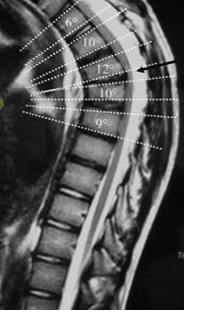

Anterior wedging

(>5deg in >3 adjacent vertebral bodies)

Cobb angle

(measures whole curvature of spine in order to determine overall impact of anterior wedging)

What is the Cobb Angle?

Used to determine the maximum angle of curvature= overall impact of antior wedging

–> guides tx of Scheuermann’s Kyphosis